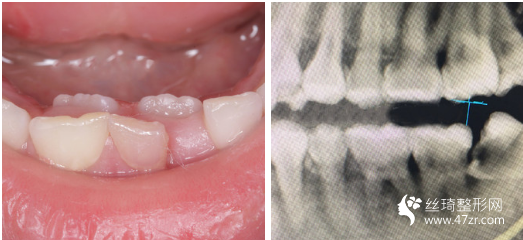

3.武漢愛(ài)齒爾口腔門診部張郭龍主治醫(yī)師案例展示

一直以來(lái),我算是一個(gè)對(duì)自己要求比較高的人,見(jiàn)不得自己有任何的瑕疵,就連牙齒也不行。 所以在我開(kāi)啟牙齒矯正路途前的三個(gè)月里,我托了較為多人進(jìn)行行業(yè)摸底(哈哈哈其實(shí)就是找個(gè)靠譜的醫(yī)生幫我做